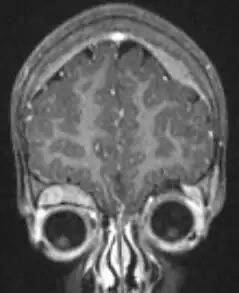

Imaging

Another way to detect neuroblastoma is the meta-iodobenzylguanidine scan, which is taken up by 90 to 95% of all neuroblastomas, often termed "mIBG-avid".[26] The mechanism is that mIBG is taken up by sympathetic neurons, and is a functioning analog of the neurotransmitter norepinephrine. When it is radio-iodinated with I-131 or I-123 (radioactive iodine isotopes), it is a very good radiopharmaceutical for diagnosis and monitoring of response to treatment for this disease. With a half-life of 13 hours, I-123 is the preferred isotope for imaging sensitivity and quality. I-131 has a half-life of 8 days and at higher doses is an effective therapy as targeted radiation against relapsed and refractory neuroblastoma.[27] As mIBG is not always taken up by neuroblastomas, researchers have explored in children with neuroblastoma whether another type of nuclear imaging, fluoro-deoxy-glucose – positron emission tomography, often termed "F-FDG-PET", might be useful.[28] Evidence suggests that this might be advisable to use in children with neuroblastoma for which mIBG does not work, but more research is needed in this area.[28]